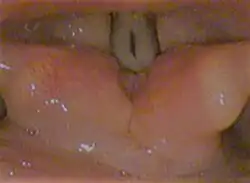

![]() Laryngoscopic view of the vocal folds. | |